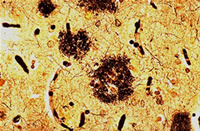

#Researchers may have pinpointed the cause of Alzheimer's disease - a rogue protein called amyloid beta (Aß) that forms plaques in the brain.